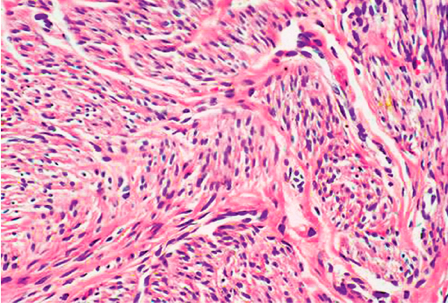

4.平滑肌肉瘤(leiomyosarcoma)

|

肉瘤细胞多呈梭形,呈轻重不等的异型性。核分裂像的多少对判定其恶性程度有重要意义。超过10个核分裂像/50个高倍视野者通常表明恶性,其他特点还有肿瘤大小(超过5cm)、坏死、浸润邻近组织和器官、高核浆比。恶性程度高者手术后易复发,可经血道转移至肺、肝及其他器官。 |